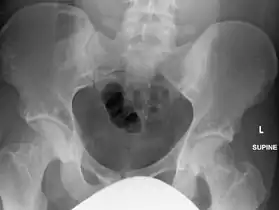

In terms of the diagnosis Osteopoikilosis is radiographically evaluated via the presence of multiple symmetrical circular sclerotic opacities [2]

The radiographic appearance of osteopoikilosis on an X-ray is characterized by a pattern of numerous white densities of similar size spread throughout all the bones. This is a systemic condition. It must be differentiated from blastic metastasis, which can also present radiographically as white densities interspersed throughout bone. Blastic metastasis tends to present with larger and more irregular densities in less of a uniform pattern. Another differentiating factor is age, with blastic metastasis mostly affecting older people, and osteopoikilosis being found in people 20 years of age and younger.